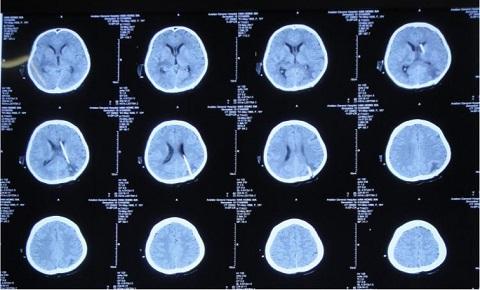

突发急诊致意识丧失的青春女孩,颅内多发感染脑积水傅继弟教授治疗

9102年5月航空总医院神经外七科傅继弟教授团队接诊一例年轻女性患者由颅内多发结核脓肿、结核性脑膜炎、脑积水病例,患者康复后再次返回校园生活。

8月16日,患者脑脊液仍然色黄浑浊,复查增强MRI现实四叠体池区、鞍区、环池内多发结核脓肿。

10月18日,患者脑脊液外观基本清亮,增强头MRI现实仍然课件鞍区多发结核脓肿、四叠体池、环池内病变明显改善。

10月20日,行分流手术,术后复查增强头MRI见图。